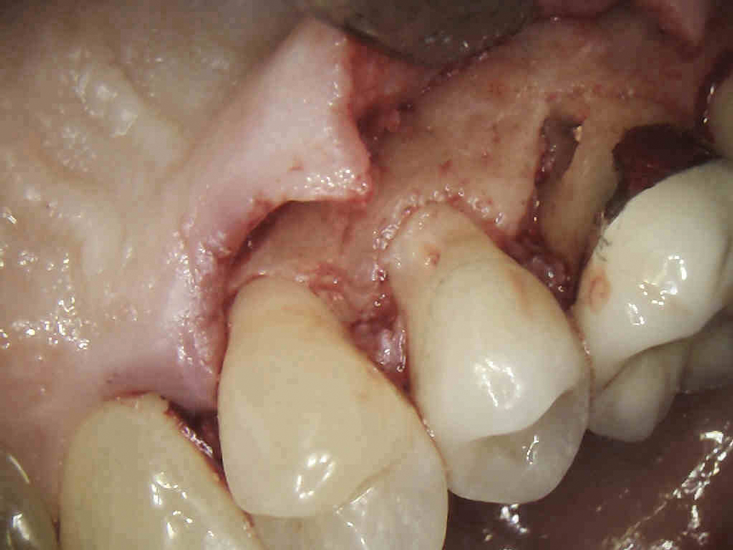

(3.) The initial surgical exposure revealed defects coronal to the crestal bone that were filled with granulation tissue and consistent with ECR.

Figure 3

(4.) The granulation tissue was removed in its entirety, and the defects were treated with a 90% TCA solution.

Figure 4

(5.) The defects were filled with a bioactive, biocompatible calcium silicate-based restorative cement.

Figure 5

(6.) Immediate postoperative view after the flap was sutured into place (Photography courtesy of Stephen Fucini, DMD).

Figure 6

If an ECR lesion is surgically accessible, external repair with gingival flap surgery is the treatment of choice (Figure 1 through Figure 6). When considering external repair, clinicians should evaluate each case for potential postoperative esthetic concerns, such as the possibility of recession following surgical repair.6,7 Moreover, clinicians should assess the overall restorability of affected teeth because the surgical repair of large ECR lesions may predispose them to fracture.6 When a Heithersay Class 1 lesion is diagnosed, nonsurgical root canal therapy (NSRCT) in addition to the surgical repair is often unnecessary. However, in Heithersay Class 2 or larger defects where pulpal involvement is suspected or confirmed, NSRCT may be necessary in addition to surgical repair.6 If NSRCT is indicated in addition to surgical repair, it is recommended that it be completed prior to surgery to avoid exacerbating pulpal disease.

The surgical repair of ECR lesions is relatively straightforward. First, a sulcular incision should be created to develop a full-thickness flap that allows for complete visualization of the resorptive defect. Subsequently, all of the resorptive tissue should be removed. Curette instrument options for resorptive tissue removal may include appropriately sized excavators, scalers, or a diamond bur in a high-speed handpiece. Next, the resorptive cavity should be cleaned, and any areas of thin dentin that prevent access to the depth of the lesion should be removed with a high-speed bur or an ultrasonic scaler. If the margin of the resorptive defect sits at the crestal bone, judicious removal of the crestal bone via crown lengthening may be necessary to avoid biologic width violation.6

Once prepared, the resorptive cavity should be treated topically with a 90% trichloroacetic acid (TCA) solution. TCA serves to eliminate any remaining clastic cells, which are known to tunnel through the dentin beyond the visible cavity margins.5 Because TCA is quite caustic, to avoid injury, care must be taken to prevent it from accidentally being applied to the bone or soft tissue.8 Place a small amount of TCA in a small glass dappen dish and apply it to the resorptive lesion with a large absorbent paper point or small cotton pellet.5 TCA causes coagulation necrosis of any residual resorption tissue; however, this effect is nonspecific, so it is crucial to apply it carefully because it can cause chemical burns to the oral mucosa or skin.8

After TCA treatment, the resorptive cavity should be restored with a biocompatible restorative material that does not wash out in saliva or gingival crevicular fluid. Due to this latter requirement, resin-modified glass ionomers are often more appropriate restorative materials in these cases than other bioceramic materials.8,9 Once restored, the patient should be recalled for follow-up appointments at 6 months and at 1 year postoperatively, at a minimum, to assess the progress of healing and for any recurrent resorption.5